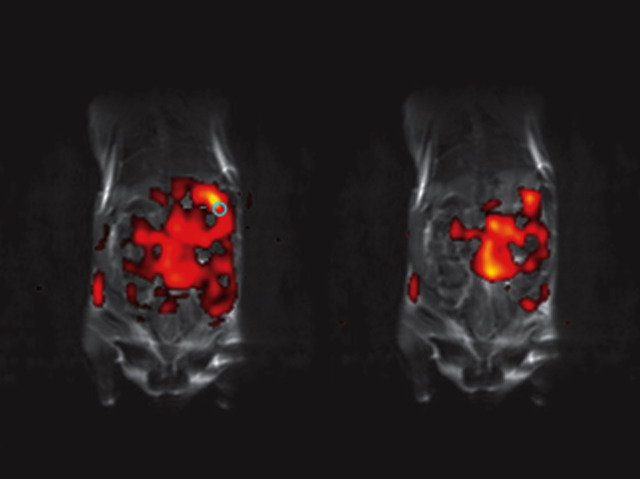

A big challenge to treating cancer is targeting chemotherapies to the right place: how can we be sure a drug hits just the spot? Here, magnetic resonance imaging (MRI) uses the magnetic properties of water molecules to map out the internal organs of a mouse (its tissues appear black, outlined in white). MRI is a widely used technology, but here it’s been taken a step further: tiny beads of silicon have been hyperpolarised, boosting their magnetic signal and making them visible under MRI. Five million times smaller than fleeing criminals captured on thermal vision cameras, the MRI follows the flow of the nanoparticles (red), from their point of injection (blue circle, left) until they settle minutes later in part of the mouse’s intestines (right hand picture). Using this visual technique on nanoparticles loaded with drugs might allow tumours to be better targeted, while watching the effects in real time.